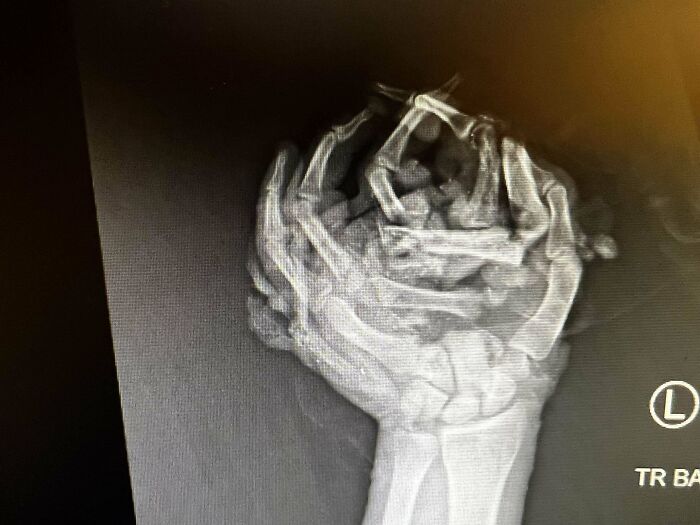

Mi mano izquierda se aplastó contra el techo de mi auto tras volcar. Radiografía de la noche del accidente.